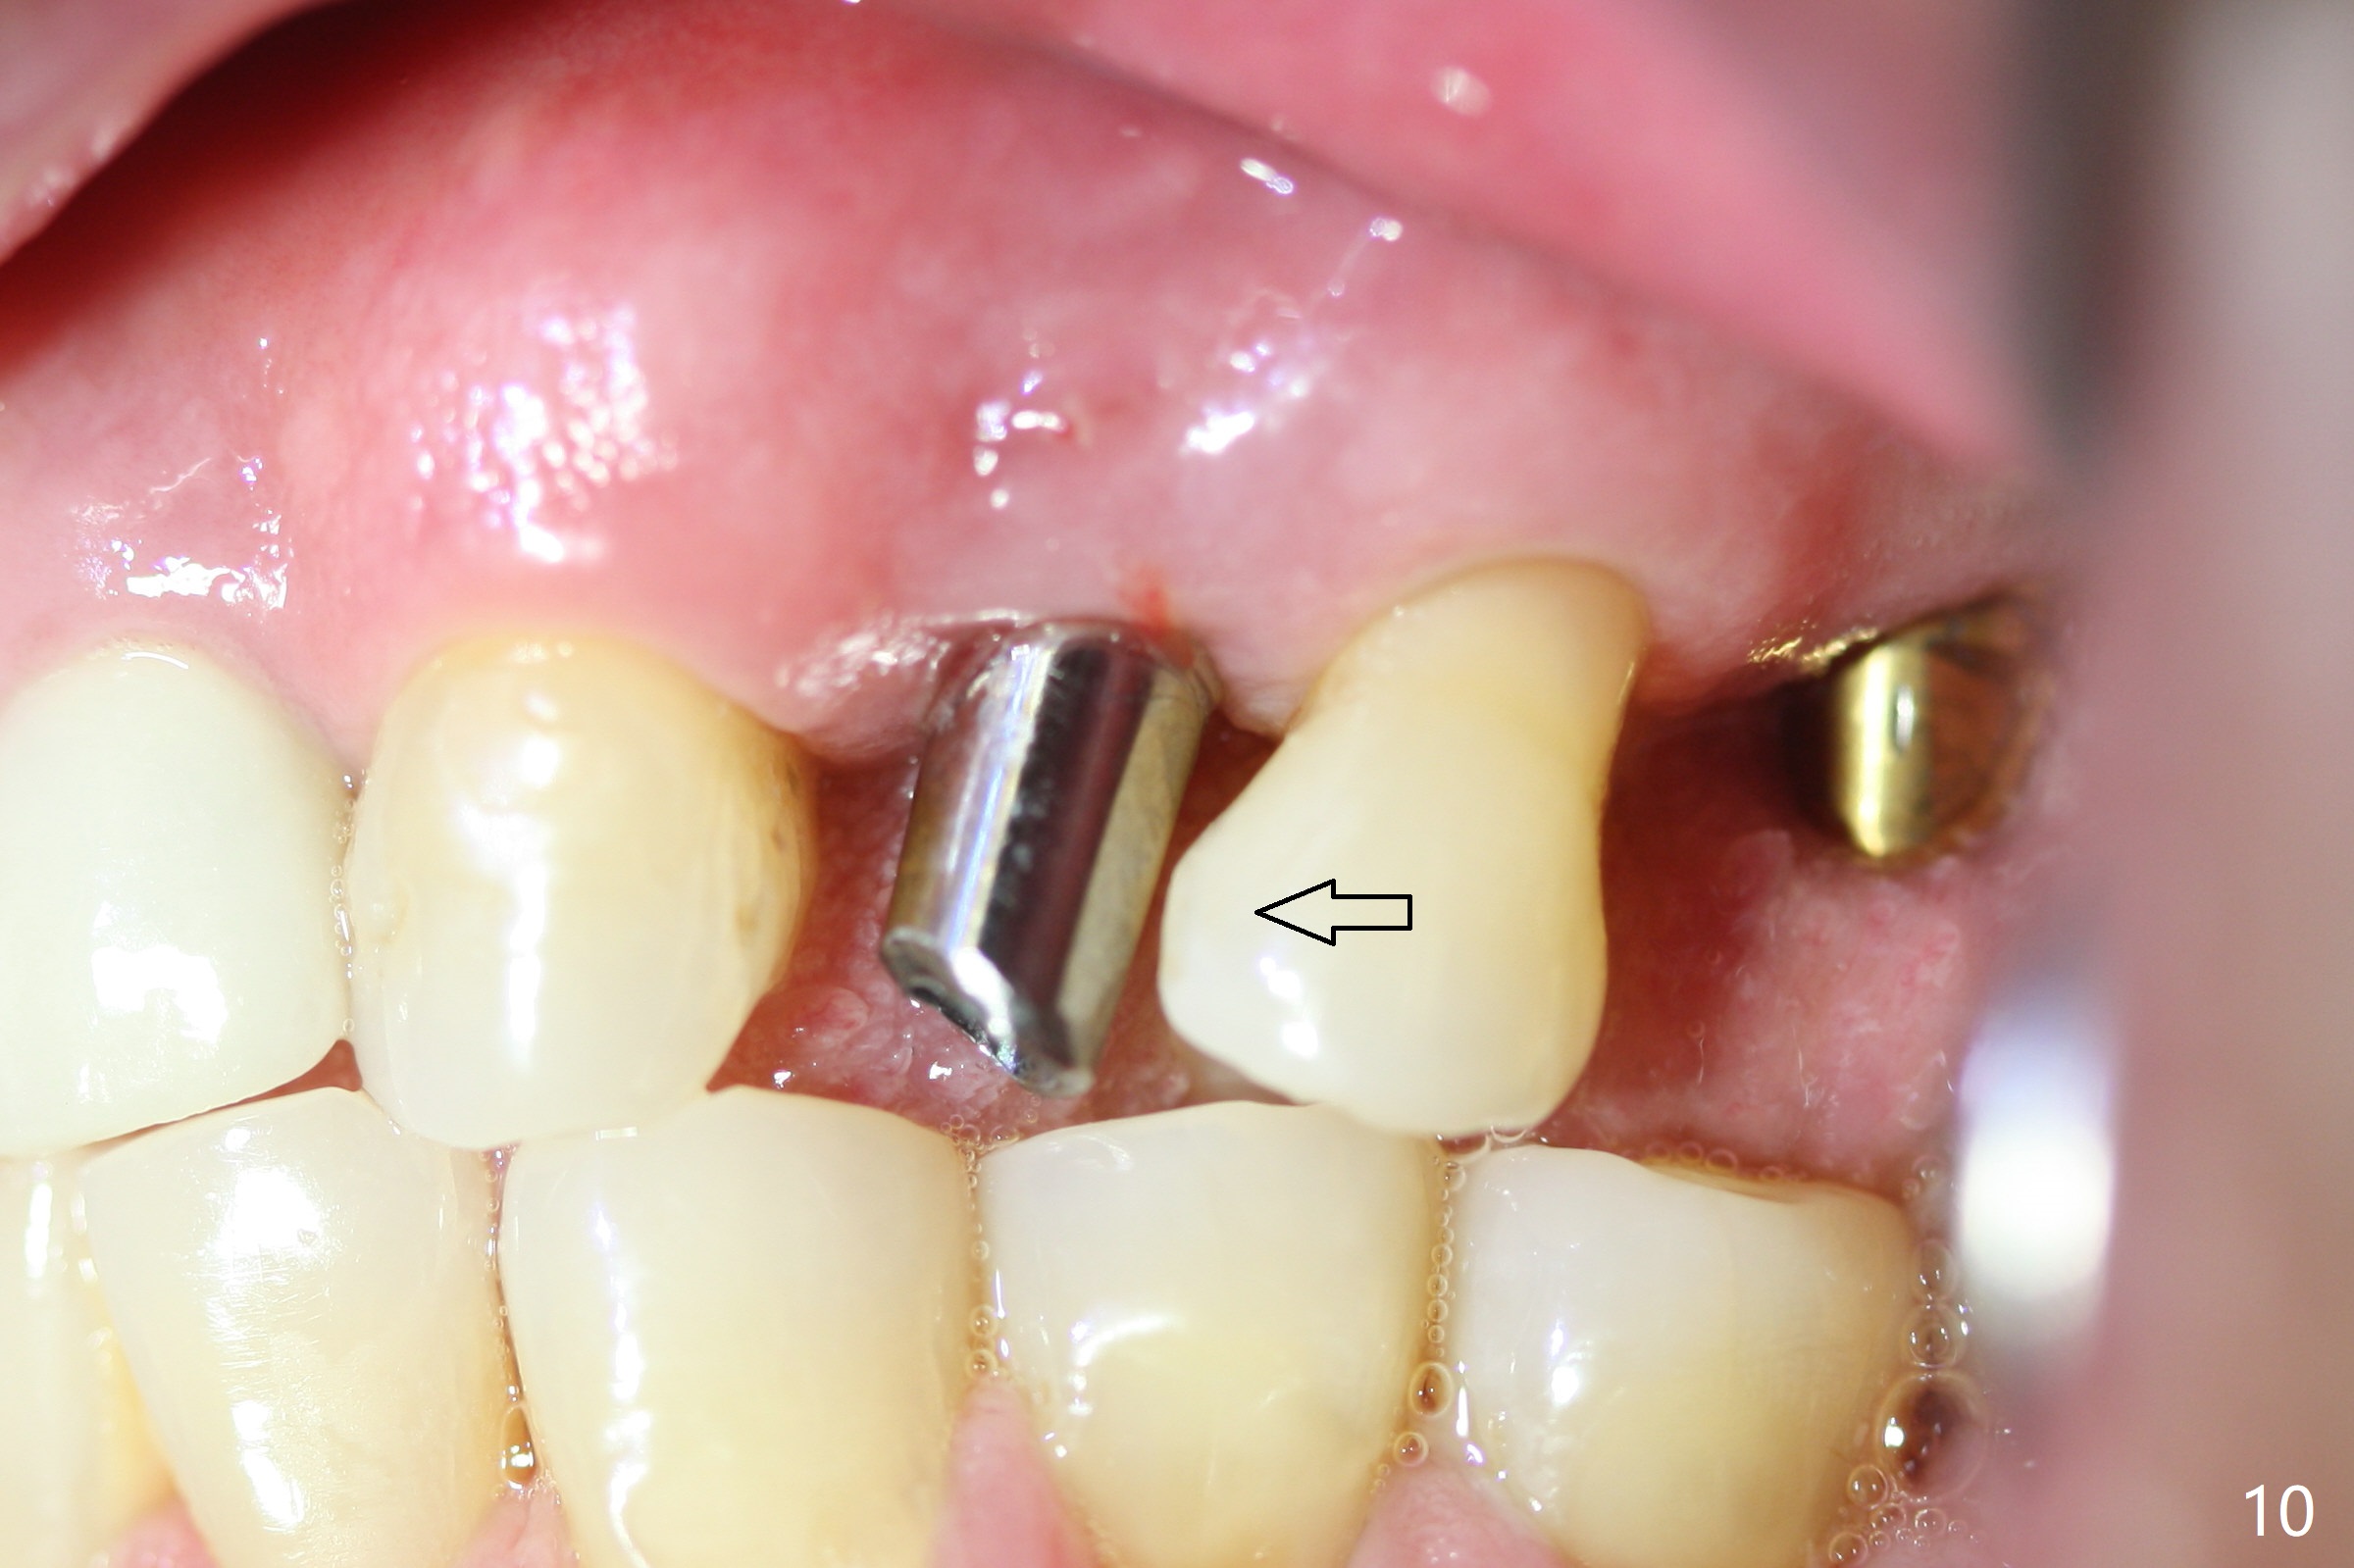

A few days prior to surgery, the tooth #12 developed abscess, self controlled by water pik (Fig.1 *). The buccal plate is defective. Initial osteotomy is close to the root of the tooth #11 (Fig.2). After adjustment of the trajectory and the depth of osteotomy (Fig.3), a 3.8x15 mm dummy implant is placed (Fig.4,5). In spite of a shorter implant (3.8x13 mm) placed deeper, approximately 7 mm implant threads are not covered buccally by the native bone (Fig.6 red dashed line). If the implant were placed deeper, the crown/implant ratio would become more unfavorable (abutment screw loosening, Fig.7). Since a mill abutment (4.5(2) mm) is inserted before Vanilla Graft, the deepest portion of the socket is unfilled (Fig.7 *). With meticulous use of a long explorer and additional allograft, the space is closed (Fig.8 *). The buccal plate collapses with apparently fistula formation 2 months postop. The patient removes the provisional for cleaning. It appears that the mill abutment is buccally placed and needs heavy reduction. The mill abutment is loose 2 months 10 days postop. When it is retightened, it tilts distal. Bone remains around the implant 6 months postop (Fig.9). Without a provisional at #12 for 5 months, the tooth #13 appears to have been shifted mesially (Fig.10 arrow). The mill abutment at #12 changes to a healing one. A lingual button is placed in the mesial surface of #13. Splinted provisional is fabricated with supraocclusion at #14 and 15 as an anchor (implants). The tooth #13 is being distalized with power chains. Limited ortho is finished nearly 2 months post banding (Fig.15,16).